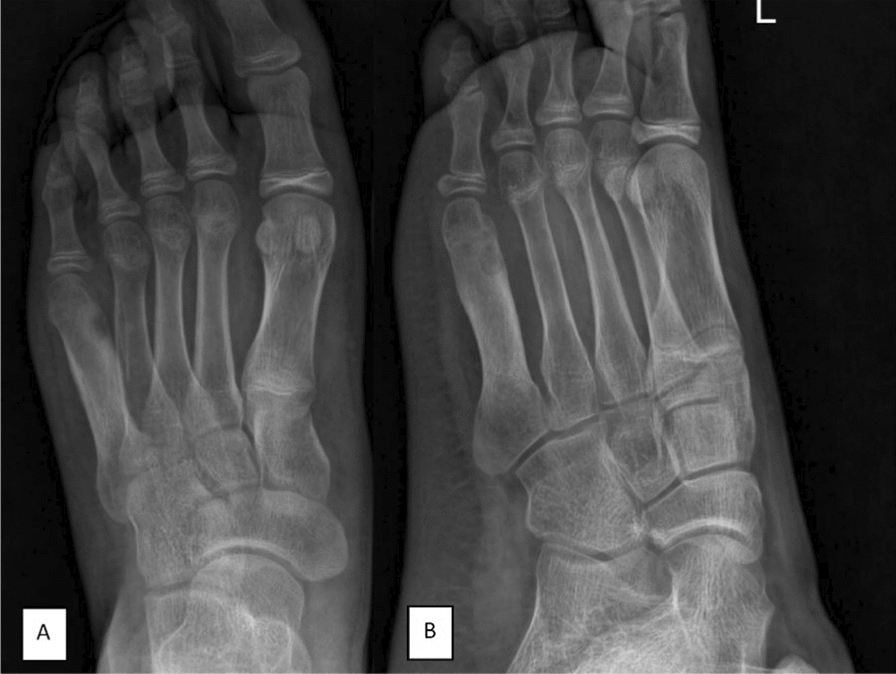

Case presentation: We report the case of a 14-year-old Persian male athlete who presented with persistent lateral forefoot pain lasting 2 years, initially attributed to a traumatic injury. The pain was progressively worsening, nocturnal, and unresponsive to nonsteroidal anti-inflammatory drugs, deviating from the classical dramatic relief associated with this tumor. Radiographs initially showed diffuse sclerosis without a visible nidus, further complicating the diagnosis. Computed tomography imaging later identified a well-defined nidus in the neck of the fifth metatarsal, confirming osteoid osteoma. Owing to the atypical symptoms, larger lesion size (> 1.5 cm), and poor response to conservative management, the patient underwent curettage and bone grafting, leading to complete symptom resolution. Histopathology confirmed the diagnosis, and postoperative follow-up showed full recovery with no recurrence at 6 months.